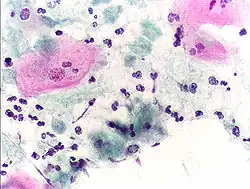

Endocervical adenocarcinoma on a pap test.

Candida organisms on a pap test.

An obviously atypical cell can be seen